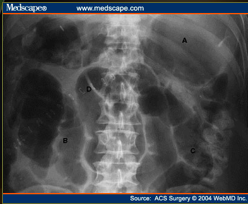

ileus: air throughout: small and large bowel look “the same”

What does the following show?

Label A-D

Post-operative ileus

A: massive gastric distention

B: distended small bowel loops

C: air in colon & mild dilatation of sigmoid colon

D: Haustral fold in apex of sigmoid colon